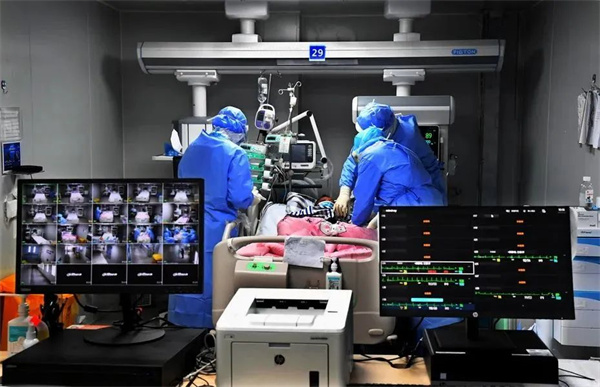

《鏖战一线》 王传顺 摄

2020 年 1 月 24 日晚,农历除夕夜,三支解放军医疗队分别从上海、重庆、西安紧急起飞,驰援湖北武汉。军队支援湖北医疗队白衣战士冲在第一线,站在最前沿,全力打好疫情防控阻击战。从 2 月 13 日到 2 月 17 日,伴随着巨大轰鸣声,11架运输机从乌鲁木齐、沈阳、西宁、天津、张家口、成都、重庆等 7 地起飞,满载着人员物资抵达天河机场。至此, 4000 多名军队医务人员列阵武汉,与来自全国各地的医疗队队员一起,全力支援武汉抗击新冠肺炎疫情。